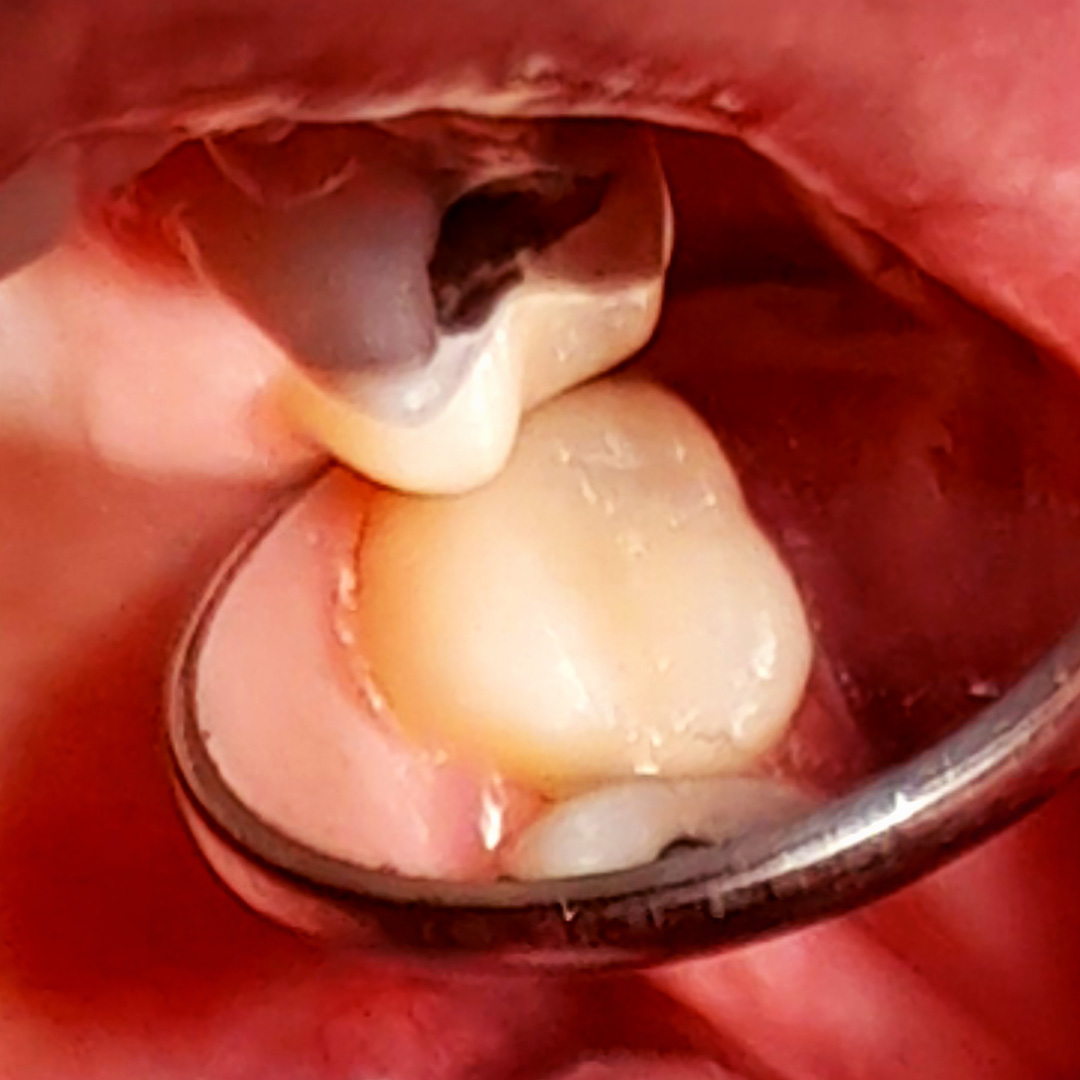

В «Стоматологию Комфорта» обратилась пациентка с жалобами на кратковременные боли от приёма холодных продуктов в области 27 зуба. В ходе осмотра врачом-стоматологом-терапевтом Похилько Н. Г. была обнаружена кариозная полость на жевательной поверхности 27 зуба. Зондирование было болезненно, перкуссия не вызвала реакции. Похилько Н. Г. провела ревизию и обработку полости под контролем кариес-маркера. Был поставлен диагноз: хронический глубокий кариес 27 зуба окклюзионно. Врач принял решение о лечении кариеса с установкой пломбы из материала Estelite.

- препарирование кариозной полости под контролем кариес-маркера;

- механическая обработка полости;